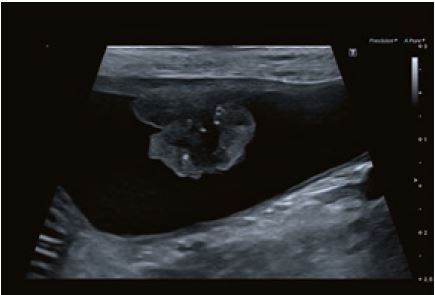

Випадок 3

Собака змішаної породи, 11 років; Гематурія; високо васкуляризоване циркулярне звуження сечового міхура з центральною вхідною судиною; хірургічне видалення з подальшою фотодинамічною терапією осередку пухлини потужністю три вати; НР: перехідно-клітинна карцинома; контрольне УЗД через шість місяців - в нормі.